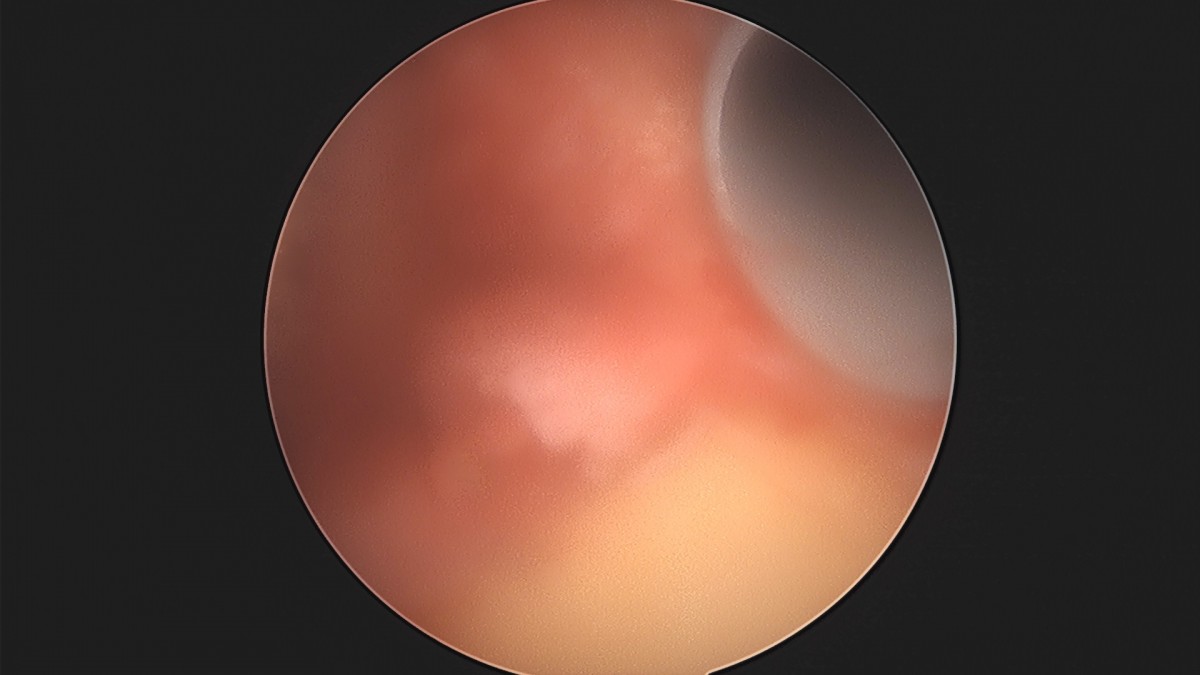

이재상원장님 어깨 견봉하 감압술 및 관절낭 이완술 박창O 환자

dae765e4d9ac96aee867c9d6292d8784_1758004611_0512.jpg